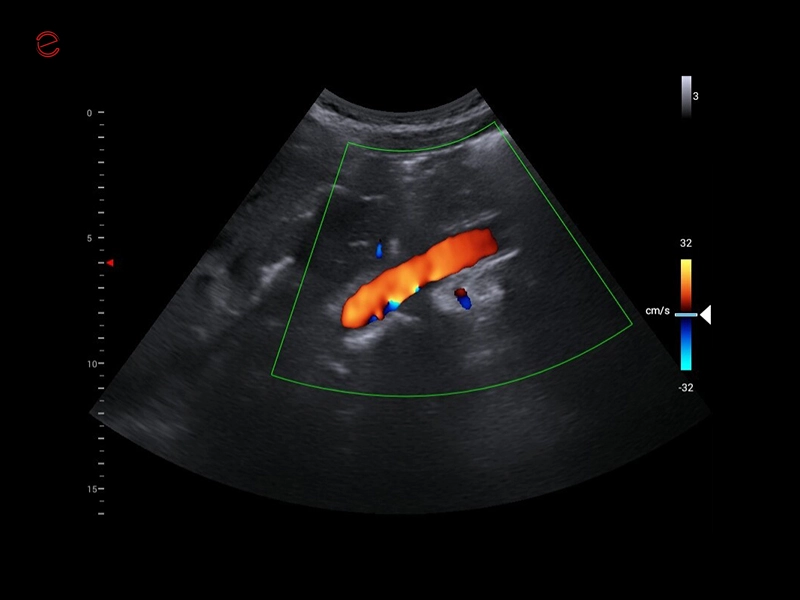

MyLab™C30 - Aorta

MyLab™C30 - Aorta